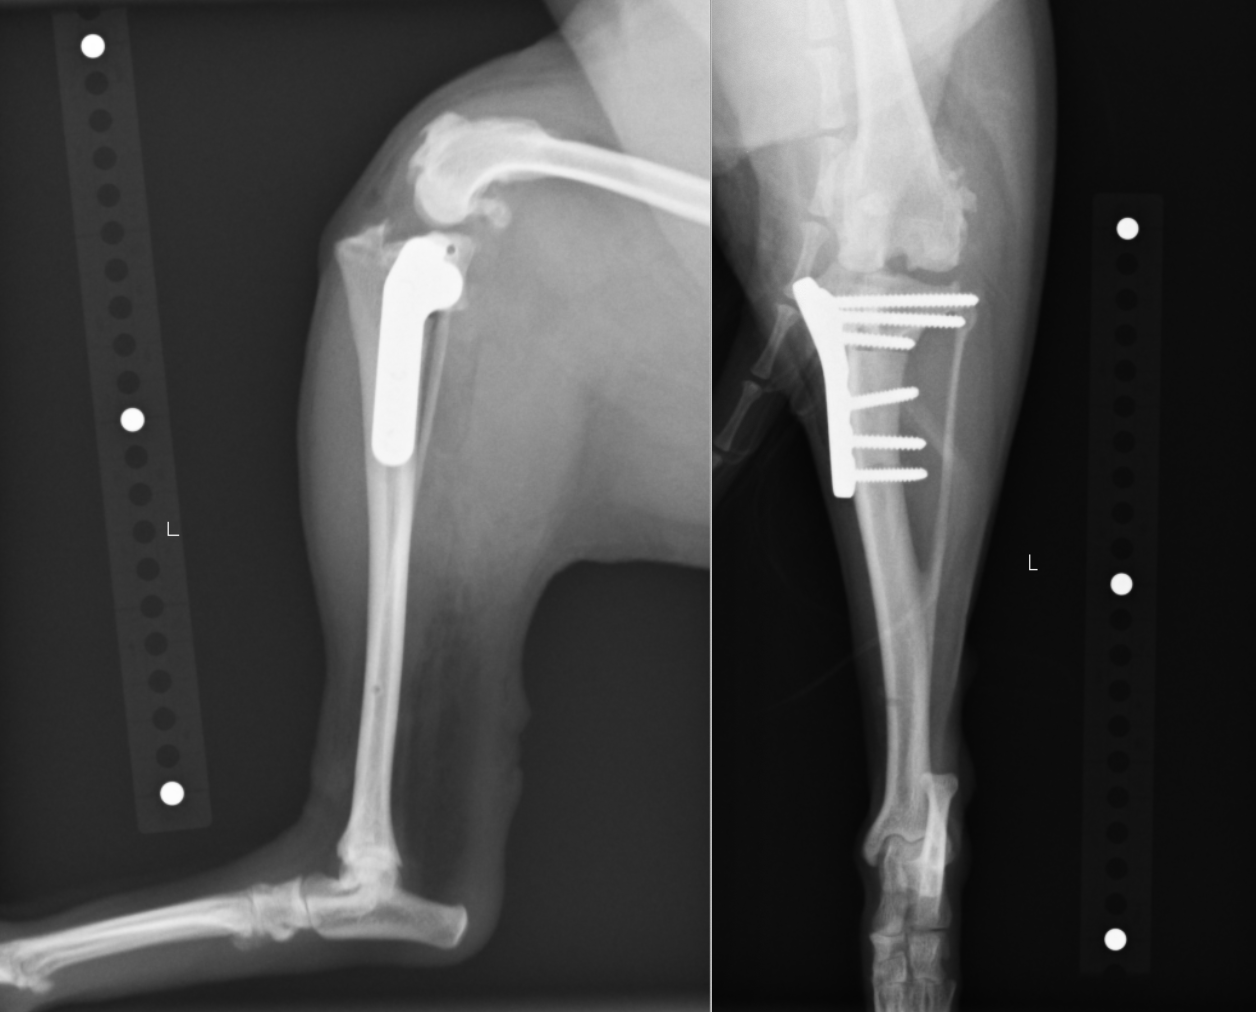

前十字靭帯断裂の膝関節です。ずれているのがおわかりでしょうか?

矢印を入れたものです。正常なものと比較すると一目瞭然でずれているのがわかるかと思います。

術後のレントゲン画像です。先程までずれていた矢印が合っているのがわかります。

またTPAと呼ばれる角度も小さくなっているのが確認できます(6°)。6°前後が理想的と言われています。